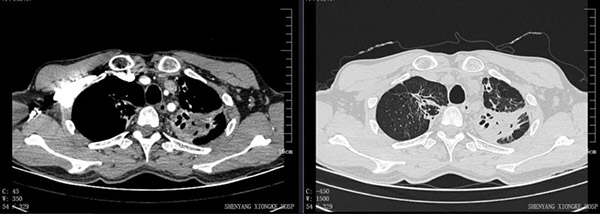

入院后经全面检查,考虑张先生左肺上叶结核合并感染(霉菌?)、双肺上叶支气管扩张、左肺上叶毁损肺。 为防止再出血及大咯血以致危及生命,手术切除已经没有功能且反复引起咯血的左上叶毁损肺是必然的。

左肺呈无功能状态,重要大血管(锁骨下动、静脉)与病灶粘连紧密。这样的肺切除极易出现血管破裂、大出血。

至此层面,整个左肺基本无功能,解剖层次不清晰。血管、支气管扭曲、变形,再次提高手术难度。

近年来结核胸外科手术大部分都是正常解剖下的肺叶、亚肺叶切除,偶有袖式肺叶切除或肺动脉、支气管双袖式切除术,作为胸外科高难手术的毁损肺切除,近年来已极少有医生去做了。究其原因主要是毁损肺病变部位粘连严重,肺门血管、支气管因肺内病变而扭曲、变形,手术处理粘连及血管时极易出现进入不了胸腔甚至血管破裂大出血,手术的难度和风险不言而喻。面对困难与挑战,丁卫忠教授带领的手术团队充分完善术前评估,针对患者的感染、贫血、营养不良等问题逐一给予纠正、控制,并与麻醉科、血库等科室反复讨论,最终制定了完备手术预案、麻醉预案。